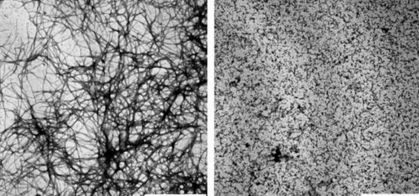

‘’One of the hallmarks of Alzheimer's disease is the abnormal clumping of beta-amyloid proteins in the brain, resulting in the death of brain cells. The discovery that small heat shock proteins prevent uncontrolled protein clumping has opened the possibility of developing drugs that emulate this effect. Now, a new study takes this a step further by revealing how small heat shock proteins interact with beta-amyloid to prevent clumping.’’